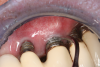

Probing as a diagnostic indicator of peri-implant disease is technique sensitive and should be done with a light probing force that is less than what is usually used around teeth (eg, force with a probe that blanches a nail bed).54 Probing evaluations are important because they can detect probing depth alterations, which may reflect peri-implant pathosis. Clinicians should note that restorative designs that limit access to the peri-implant crevice can complicate probing assessments (Figure 1).

Fig 1. Probing is essential in monitoring the health of peri-implant

tissues. The design of this maxillary hybrid prosthesis interferes with

circumferentially probing the implants.

Figure 1